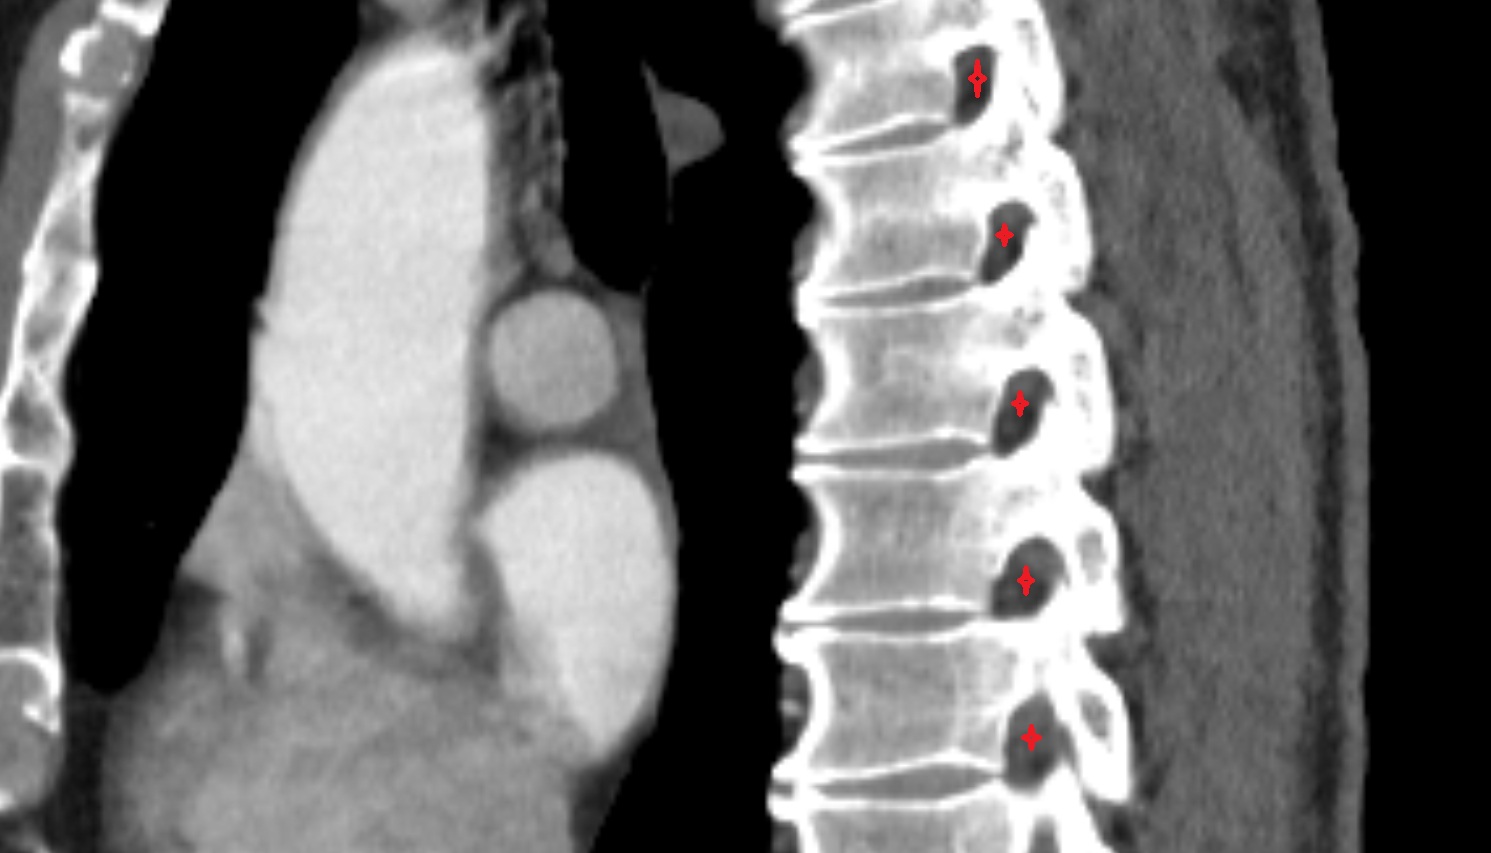

- L4–L5 Intervertebral Disc

- L3–L4 Intervertebral Disc

- L2–L3 Intervertebral Disc

- L1–L2 Intervertebral Disc

- T12–L1 Intervertebral Disc